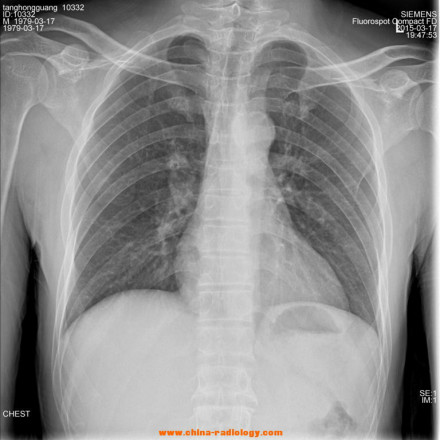

X射线诊断

X射线应用于医学诊断,主要依据X射线的穿透作用、差别吸收、感光作用和荧光作用。由于X射线穿过人体时,受到不同程度的吸收,如骨骼吸收的X射线量比肌肉吸收的量要多,那么通过人体后的X射线量就不一样,这样便携带了人体各部密度分布的信息,在荧光屏上或摄影胶片上引起的荧光作用或感光作用的强弱就有较大差别,因而在荧光屏上或摄影胶片上(经过显影、定影)将显示出不同密度的阴影。根据阴影浓淡的对比,结合临床表现、化验结果和病理诊断,即可判断人体某一部分是否正常 。

1、感光作用。X射线同可见光一样能使胶片感光。胶片感光的强弱与X射线量成正比,当X射线通过人体时,因人体各组织的密度不同,对X射线量的吸收不同,胶片上所获得的感光度不同,从而获得X射线的影像 。